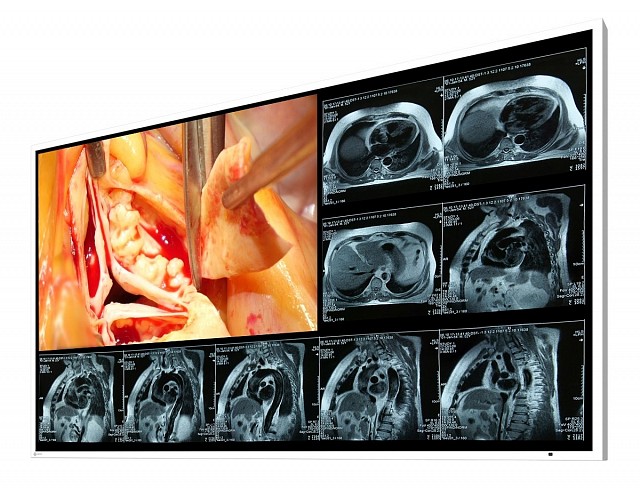

EIZO stellt neuen großflächigen Monitor für den Operationssaal vor

Die EIZO GmbH kündigt heute einen neuen 49“ Monitor zur Wandmontage im Operationssaal (OP) an. Der LX490W ist ein Breitbild-Monitor mit Full HD Auflösung, der ideal für das Betrachten von medizinischen Bildern (Röntgen, CR, MRI oder Endoskopie) im OP ist.